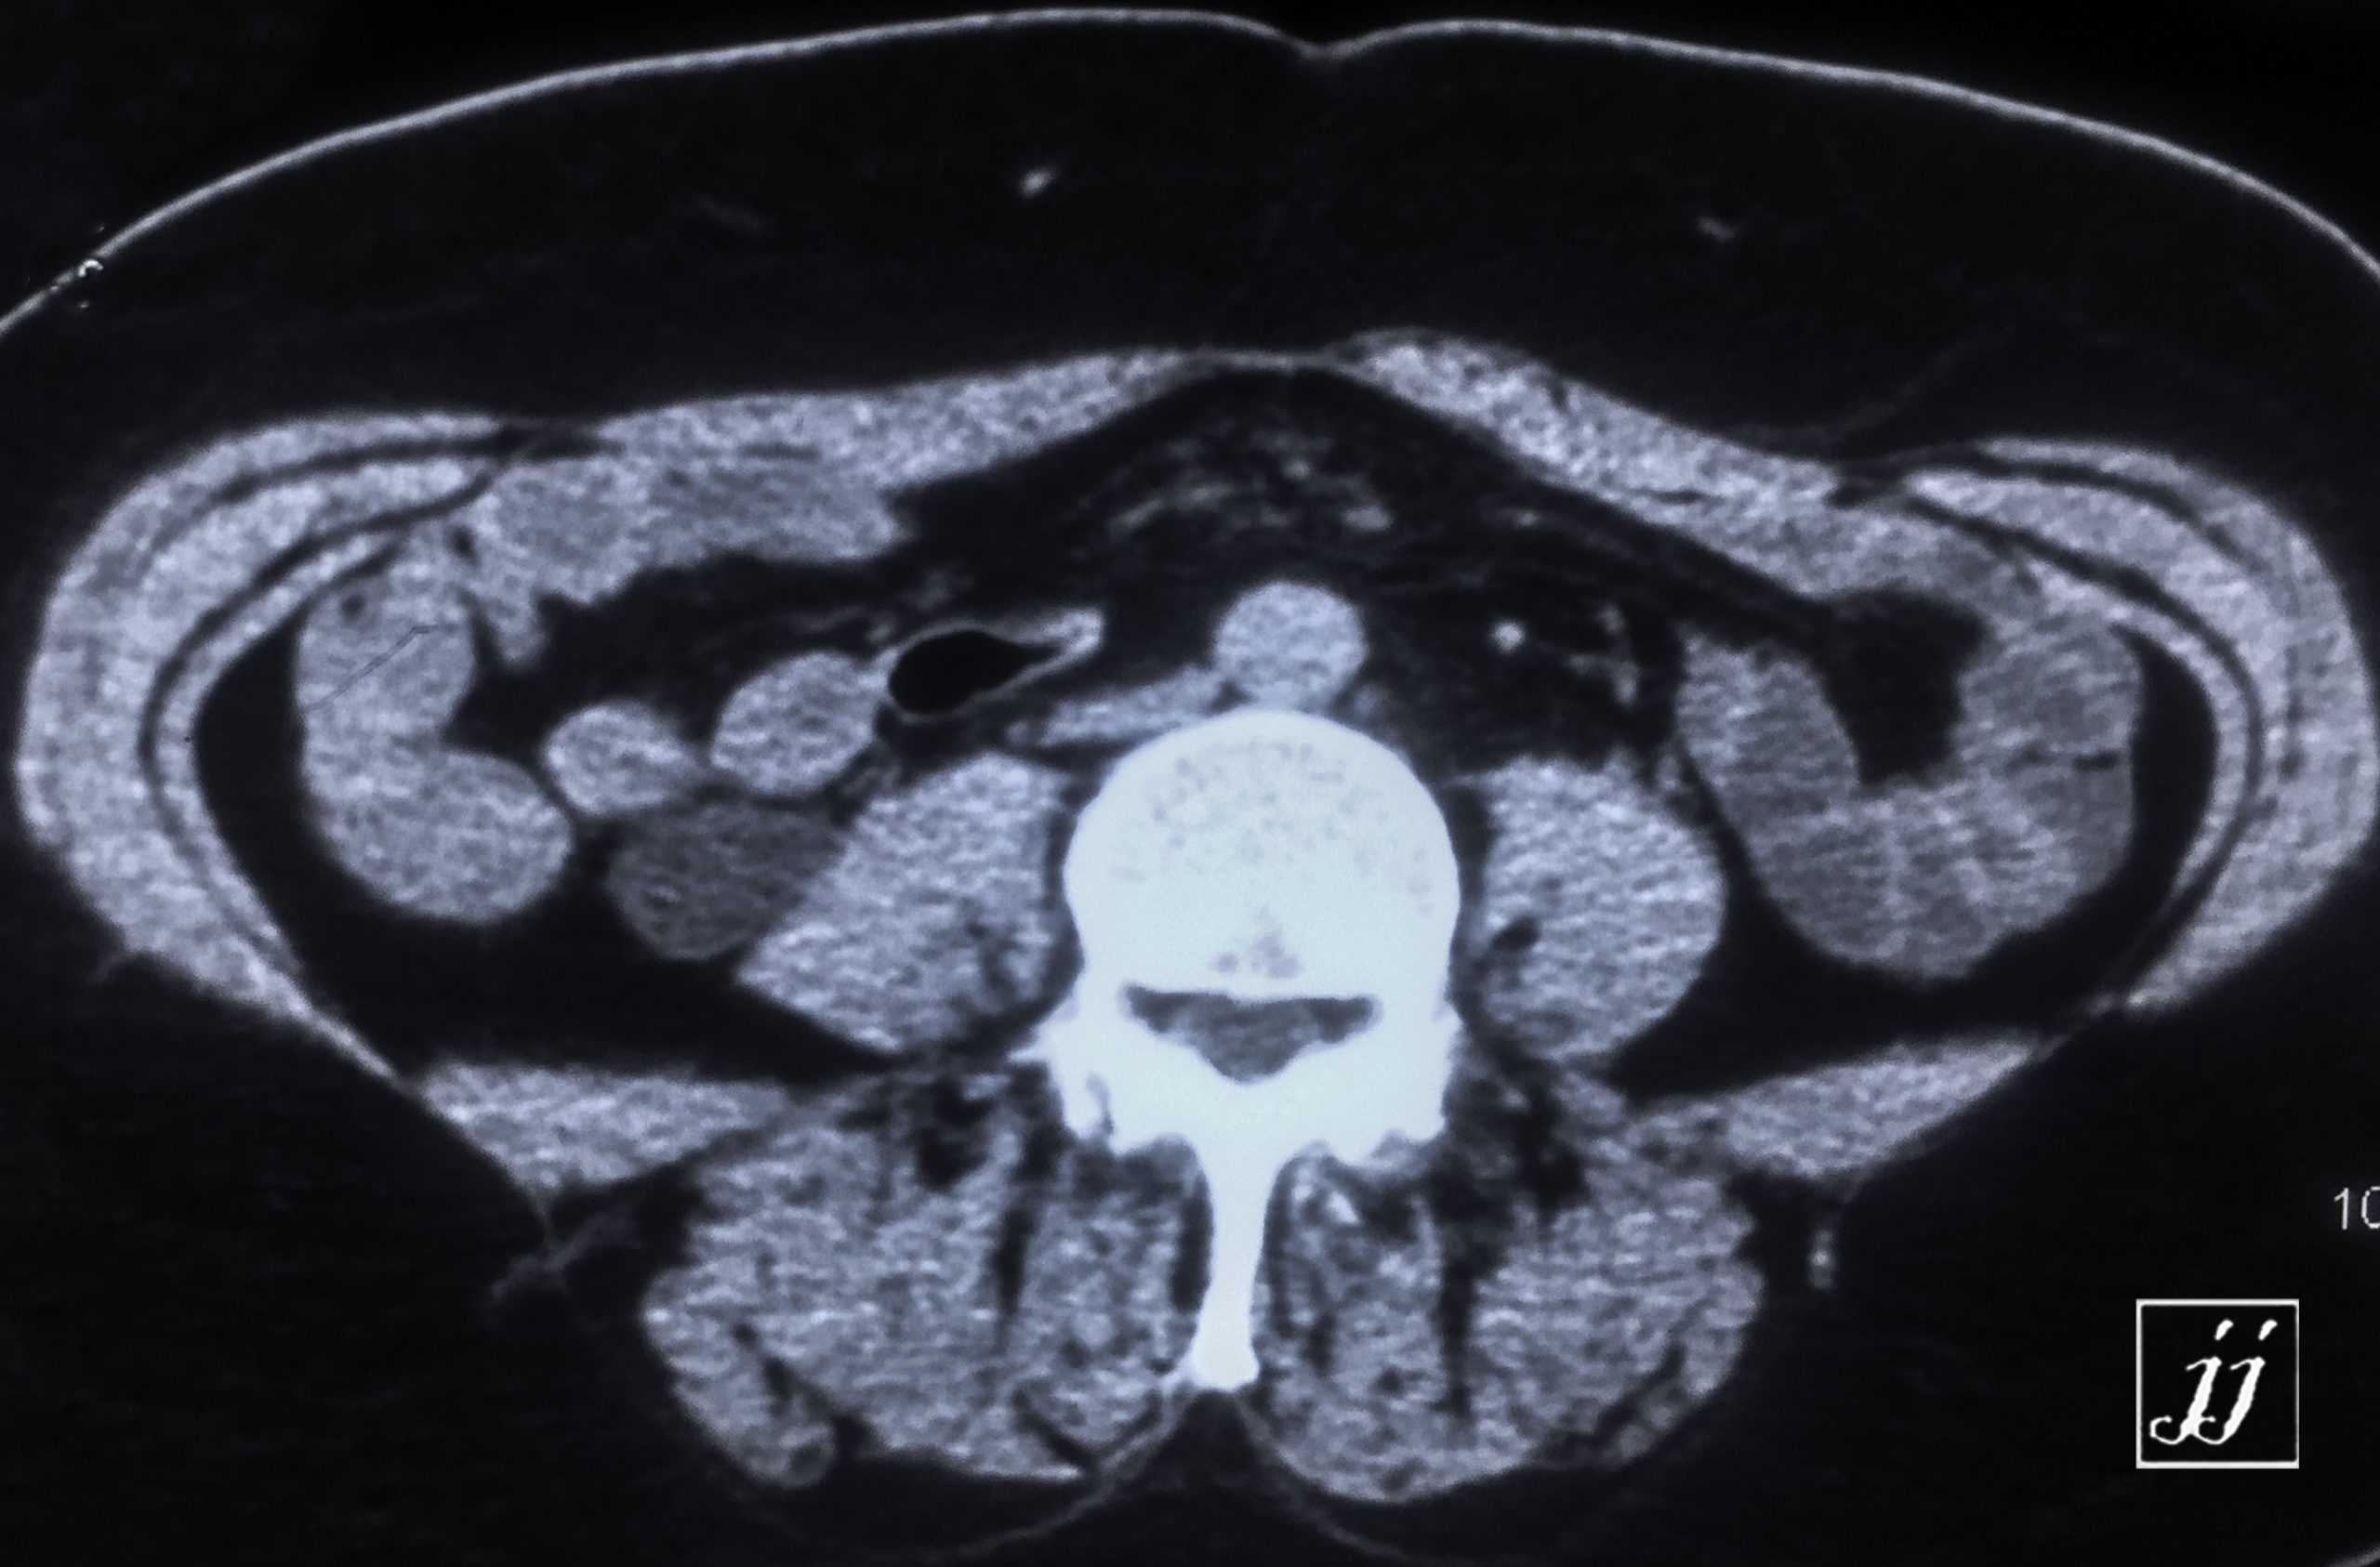

Abdomen- right side severe hydronephrosis and ureter (25)